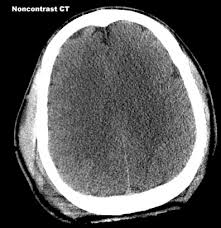

Diffuse cerebral swelling with delayed catastrophic deterioration, a known complication of brain trauma, has been postulated to occur after repeated concussive brain injury in sports--the "second impact syndrome" (SIS). Certain current concussion management guidelines are contingent upon this assumption. We established criteria for definite, probable, and possible SIS and analyzed all published cases. A total of 17 cases were identified in which the reports described the cases as being consistent with SIS. Of these, only five probable cases of SIS were found based on our diagnostic criteria. We also studied the accuracy of recalled episodes of minor concussion in football players by their teammates because the diagnosis of SIS is usually based on such accounts. We found overreporting of recalled episodes of concussion in teammates when compared with self reports and videotape analysis. Based on case reports, the claim that SIS is a risk factor for diffuse cerebral swelling is not established. Prevention strategies for sports-related cerebral swelling are difficult to implement in the absence of established risk factors.

Second impact syndrome is believed to be the catastrophic consequence of repeated head injury in sport. The scientific evidence to support this concept is nonexistent, and belief in the syndrome is based upon the interpretation of anecdotal cases more often than not, lacking sufficient clinical detail to make definitive statements. The fear of this condition has driven many of the current return-to-play guidelines following concussion. Diffuse cerebral swelling (DCS) following a head injury is a well-recognized condition, more common in children than in adults, and usually has a poor outcome.